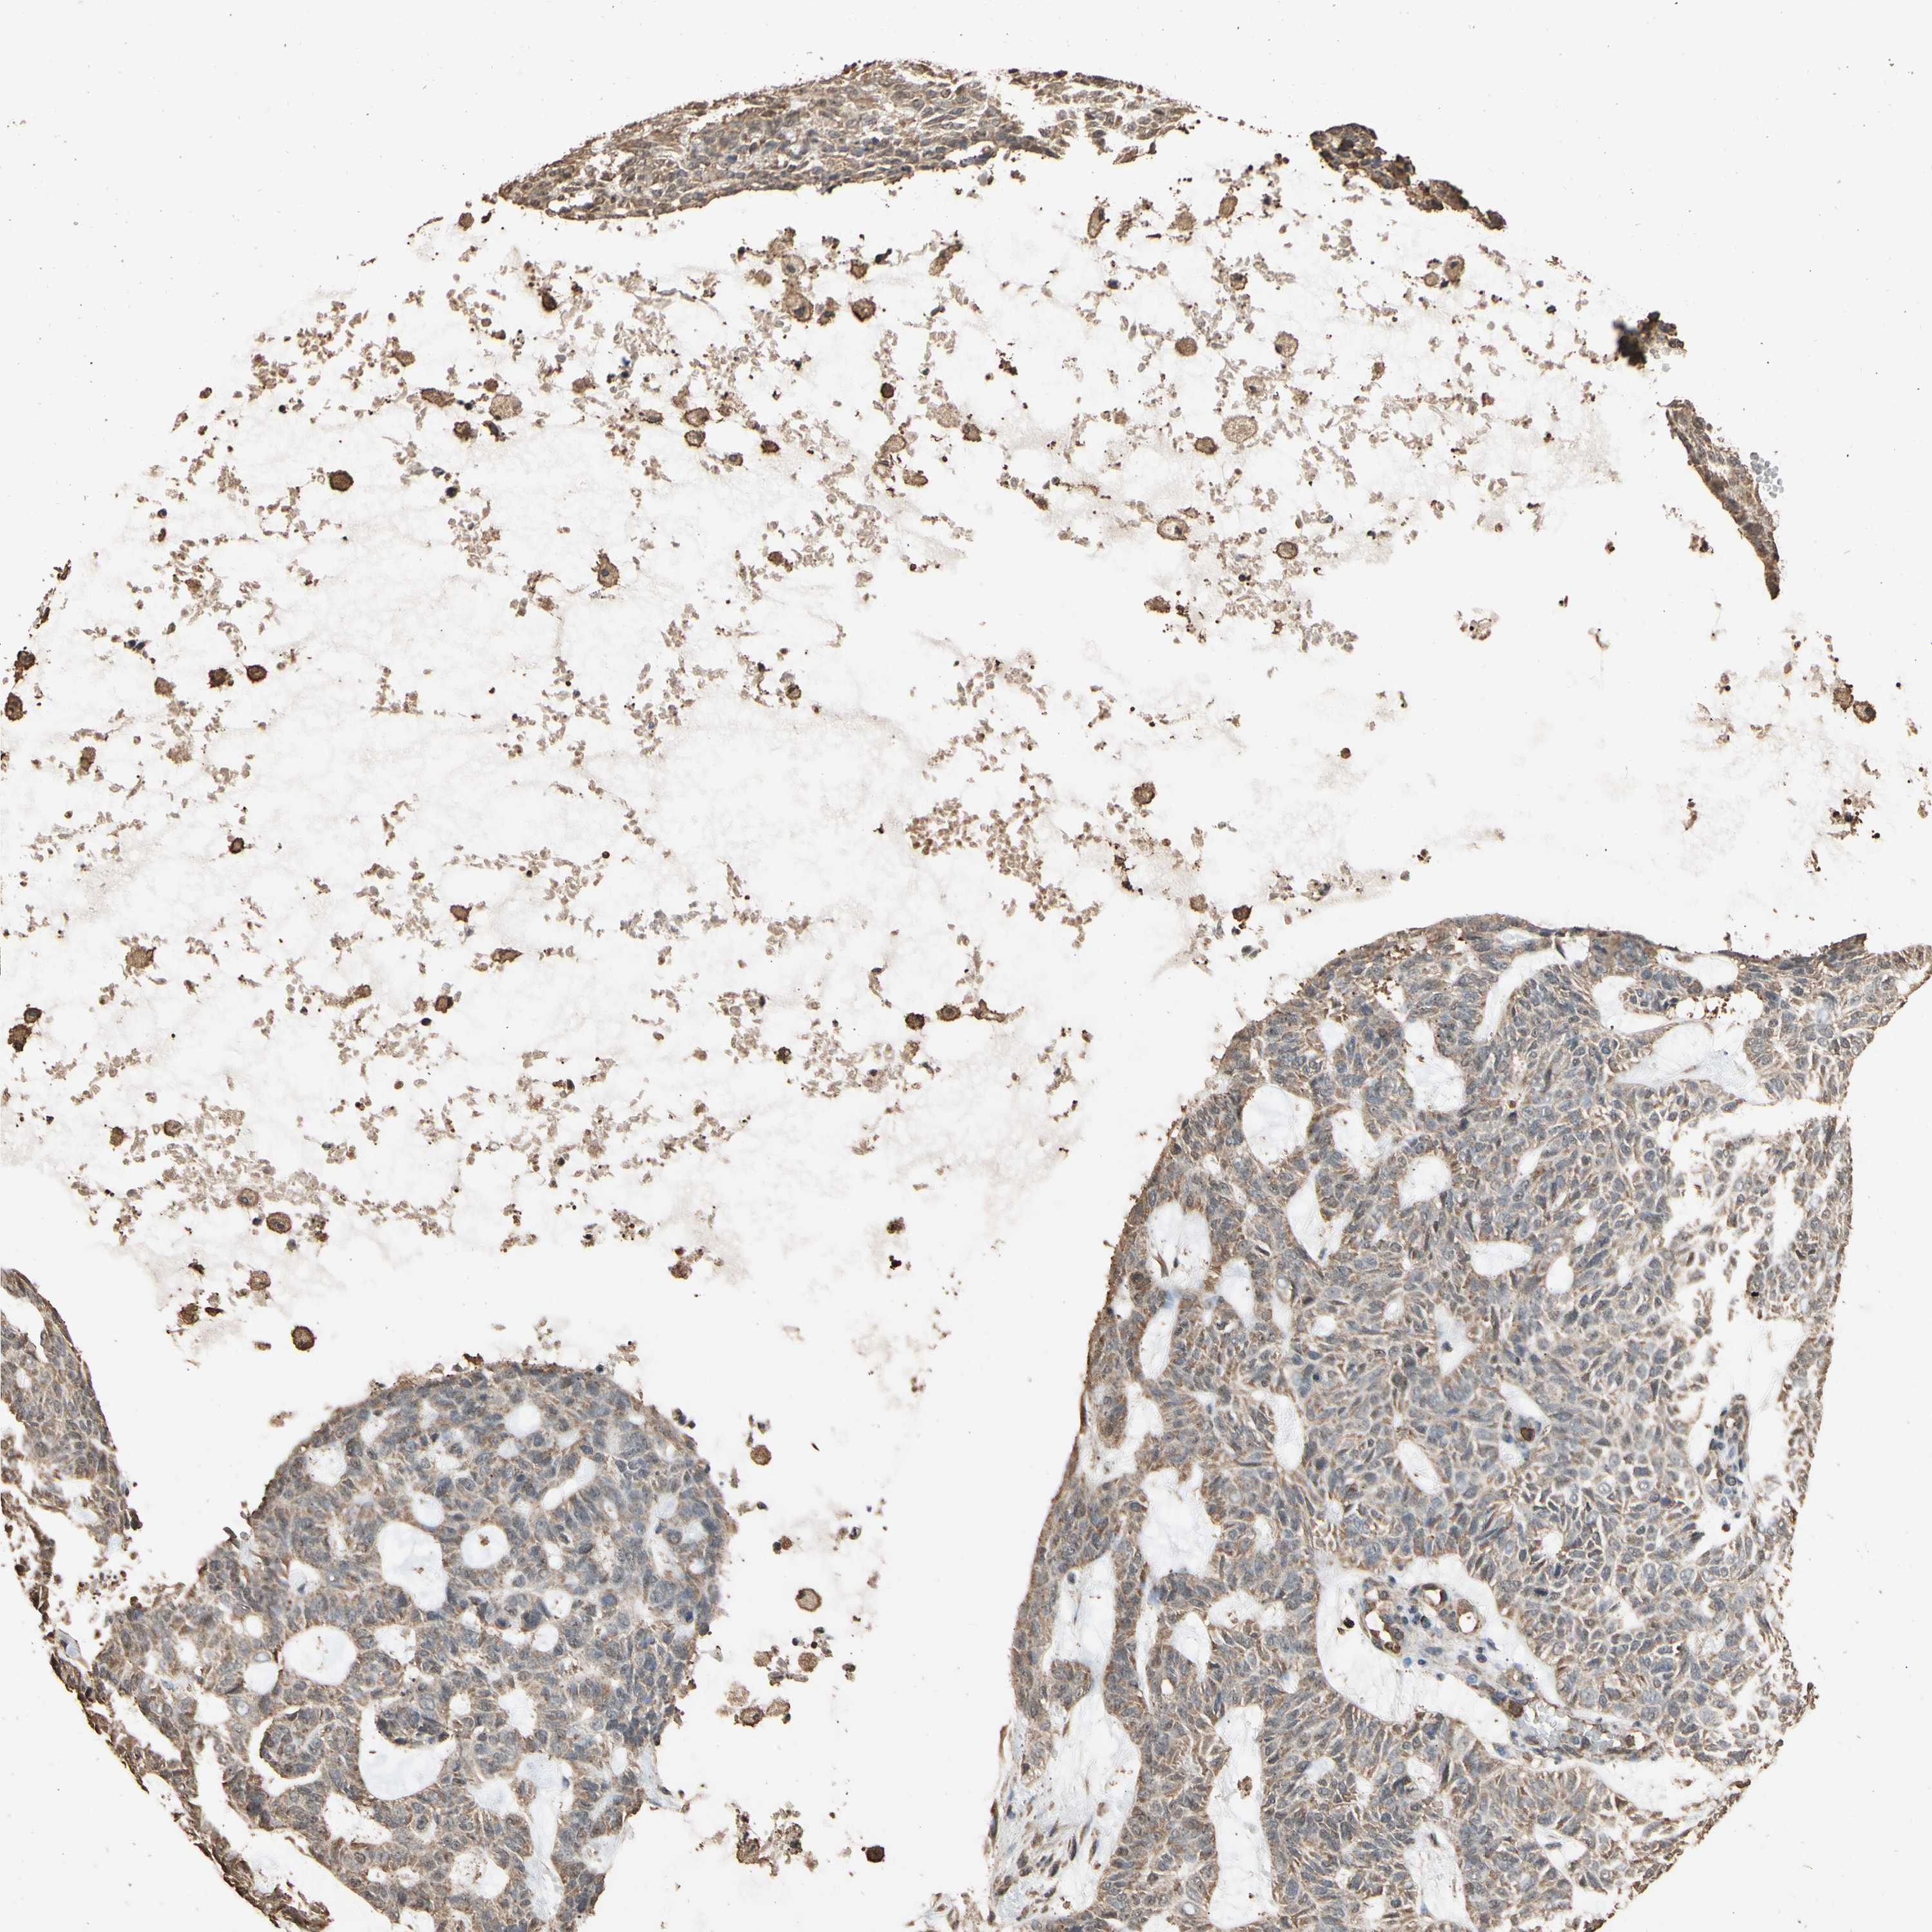

Basal cell and squamous cell cancer

SKIN CANCER - Protein expressioni

A mouse-over function shows sample information and annotation data. Click on an image to view it in a full screen mode. Samples can be filtered based on level of antibody staining by selecting one or several of the following categories: high, medium, low and not detected. The assay and annotation is described here.

Antibody stainingi

Antibody staining in the annotated cell types in the current human tissue is reported as not detected, low, medium, or high, based on conventional immunohistochemistry profiling in selected tissues. This score is based on the combination of the staining intensity and fraction of stained cells.

Each image is clickable and will lead to virtual microscopy that enables deeper exploration of all samples and also displays staining intensity scores, fraction scores and subcellular localization as well as patient and tissue information for each sample.

Antibody CAB009188

Staining

High

Medium

Low

Not detected

Intensity

Strong

Moderate

Weak

Negative

Quantity

>75%

75%-25%

<25%

None

Location

Nuclear

Cytoplasmic/membranous

Cytoplasmic/membranous,nuclear

Squamous cell carcinoma, NOS

Basal cell carcinoma